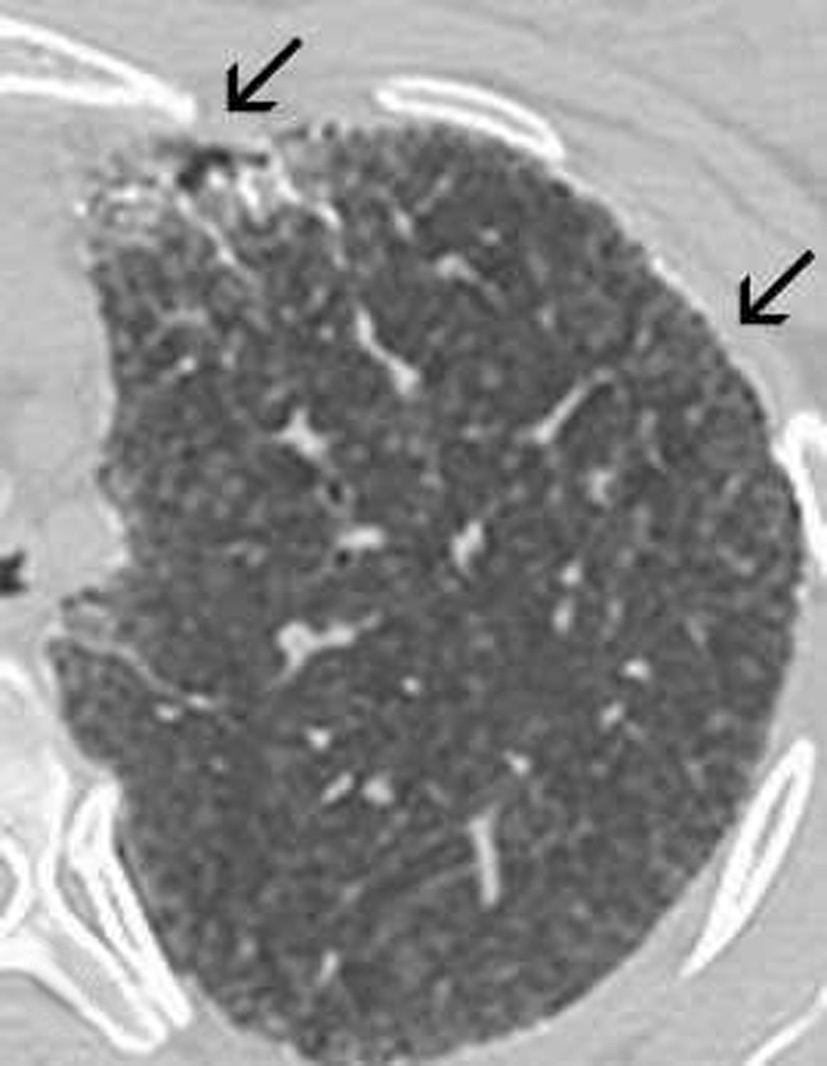

Las imágenes demostraron la presencia de puntiformes y difusas calcificaciones bilaterales, de predominio subpleural, en pleura mediastínica y en los septos interlobulillares. Los segmentos posteriores e inferiores estaban mayoritariamente afectos (fig. 2). También se visualizaron nódulos calcificados a nivel de segmentos anteriores (fig. 2B). El estudio detallado de alta resolución demostró un "patrón en empedrado" o crazzy-paving con marcado engrosamiento de los septos interlobulillares asociado a áreas parcheadas de aumento de la densidad en "vidrio deslustrado" o ground-glass, con mayor afectación de los segmentos posterobasales (figs. 3A y B). A nivel de los lóbulos superiores también se evidencian pequeños quistes subpleurales (fig. 3C).

Fig. 3. Las imágenes tomográficas de alta resolución demuestran la presencia de áreas mal definidas de aumento de densidad en vidrio deslustrado o ground-glass, con moderado engrosamiento de los septos interlobulillares, principalmente en los segmentos anteriores, adoptando en conjunto un "patrón en empedrado" o crazy-paving pattern (A). Secciones inferiores (B) demuestran la mayor afectación de las bases pulmonares. (C) También pueden visualizarse pequeños quistes subpleurales (flechas).